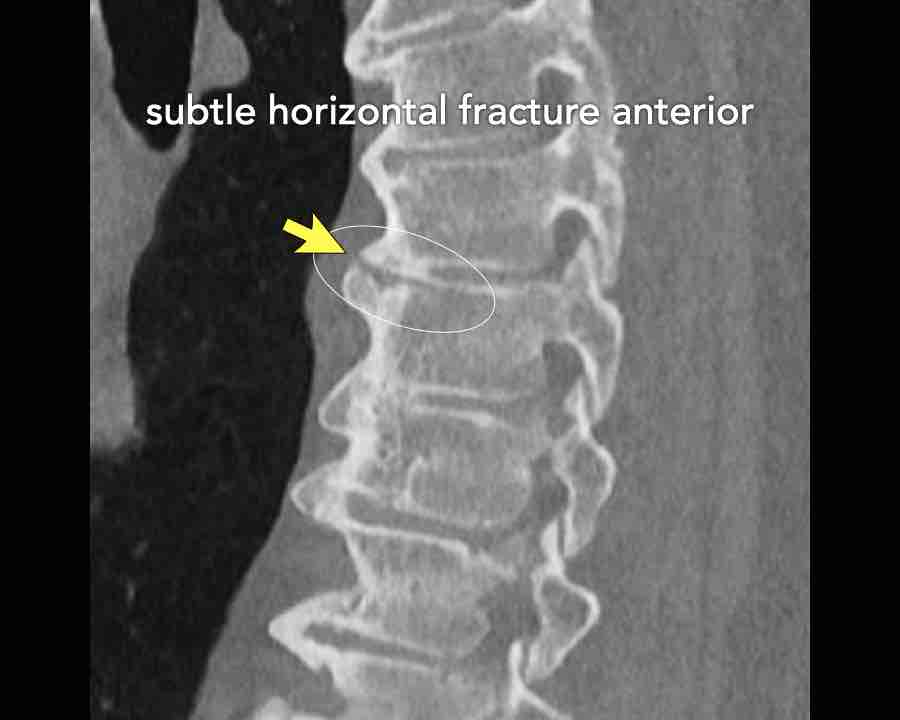

Scroll through images.

What are the findings?

Findings

- C injury? No.

- Signs of a rigid spine?

Yes, so be aware of potentially very subtle B3 injury. - A subtle fracture on the anterior vertebral body is seen (arrows).

Conclusion

Injury type B3.